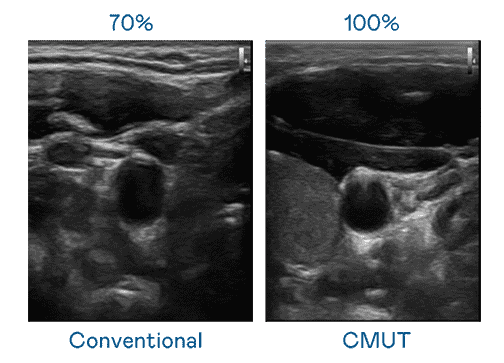

CMUT 技术是一种用电容式微机电元件来产生超音波讯号的技术。。。与传统 PZT 压电式技术相比,,CMUT 频宽增加 30%,,,,更宽频的超音波讯号让影像解析度大幅提升,,,是实现高影像品质医疗超音波扫描、、促进精准医疗发展的关键技术。。

大频宽带来超清晰影像

超音波影像的解析度高低,,,,首先取决于探头能发出的讯号频宽。。918.COM CMUT 可提供高清晰的超音波讯号,,提供高频宽、、、高灵敏度、、、影像纹理细节更高的超音波影像,,,,协助医护人员缩短影像判读时间及利用精准的医疗影像进行诊断。。